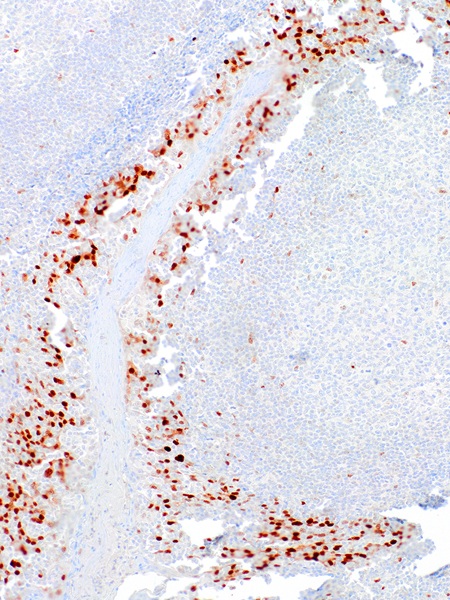

Immunohistochemical staining of human tonsil tissue using Cyclin D1 Rabbit Monoclonal Antibody (ARM972).